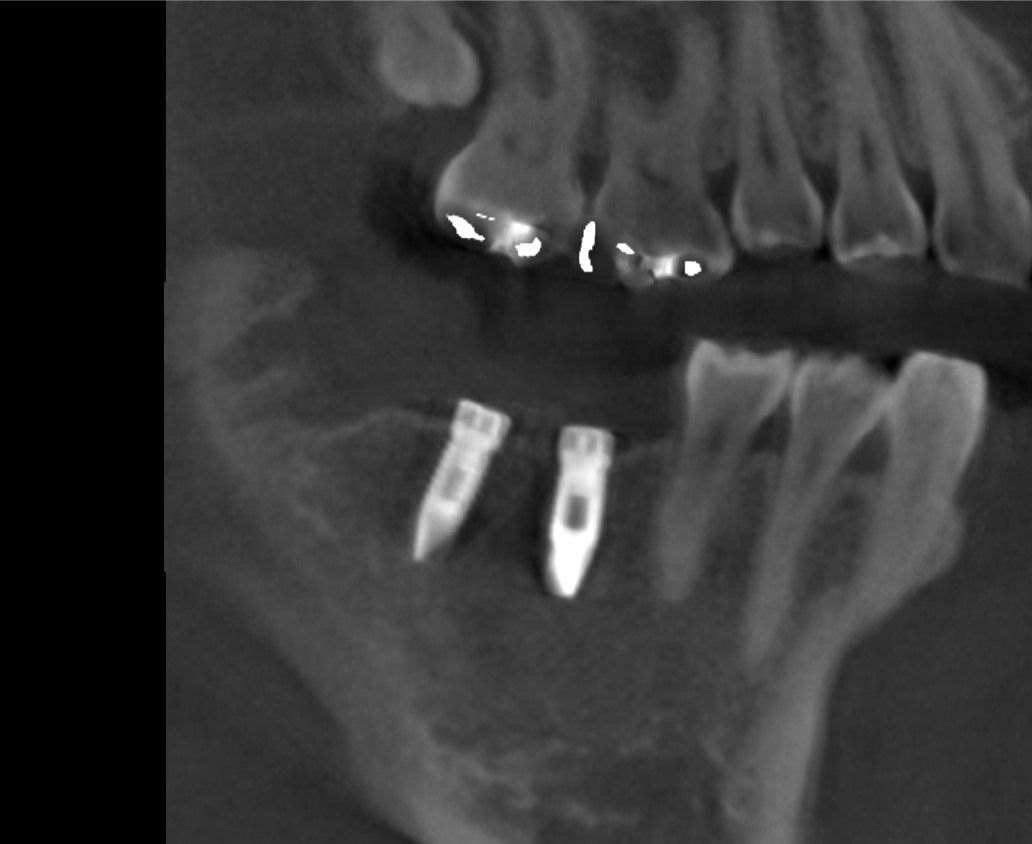

先日インプラントの型取をした患者さんの被せ物が出来上がってきました。

これをネジを使ってインプラントに接続します。